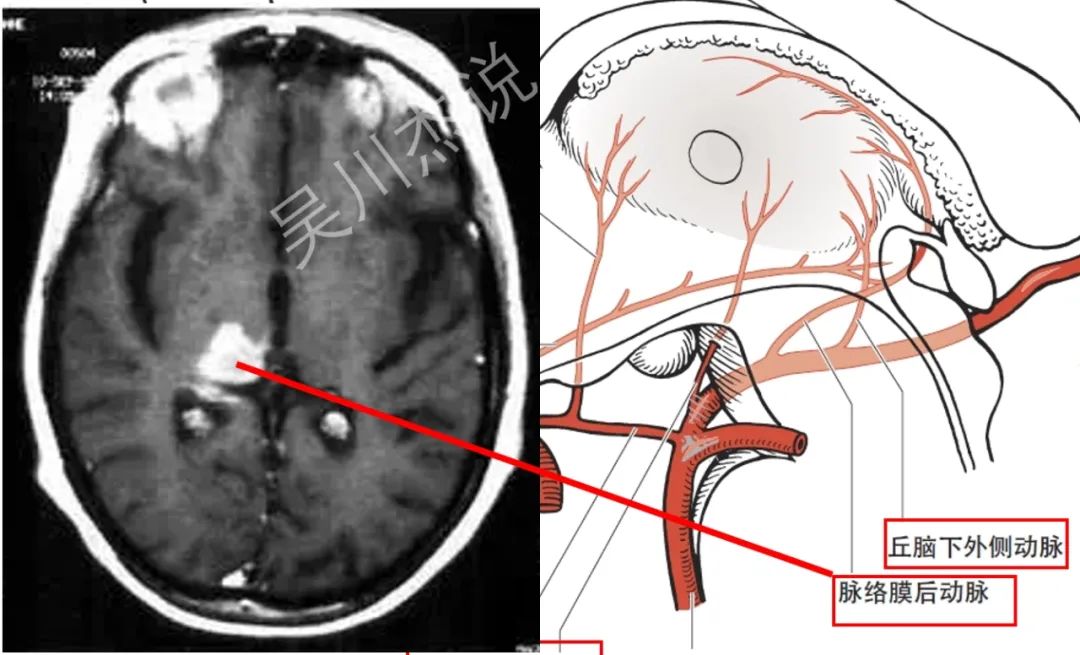

• 丘脑下外侧动脉:又称丘脑膝状体动脉,起自大脑后动脉P2段。朋友们,抛弃这个难以记忆的丘脑膝状体动脉的称呼,丘脑下外侧动脉当然是供应丘脑的下外侧部分了。

• 脉络膜后动脉:起自大脑后动脉P2段。貌似最后丘脑大概南极位置的血供就只剩下脉络膜后动脉来供应了吧。

放大一点,我们再来看看上图中这4根动脉的供血范围。

我们再来看看一个立体的模式图,从另外一个角度再来理解一下这四根动脉的起源、走形和分布。